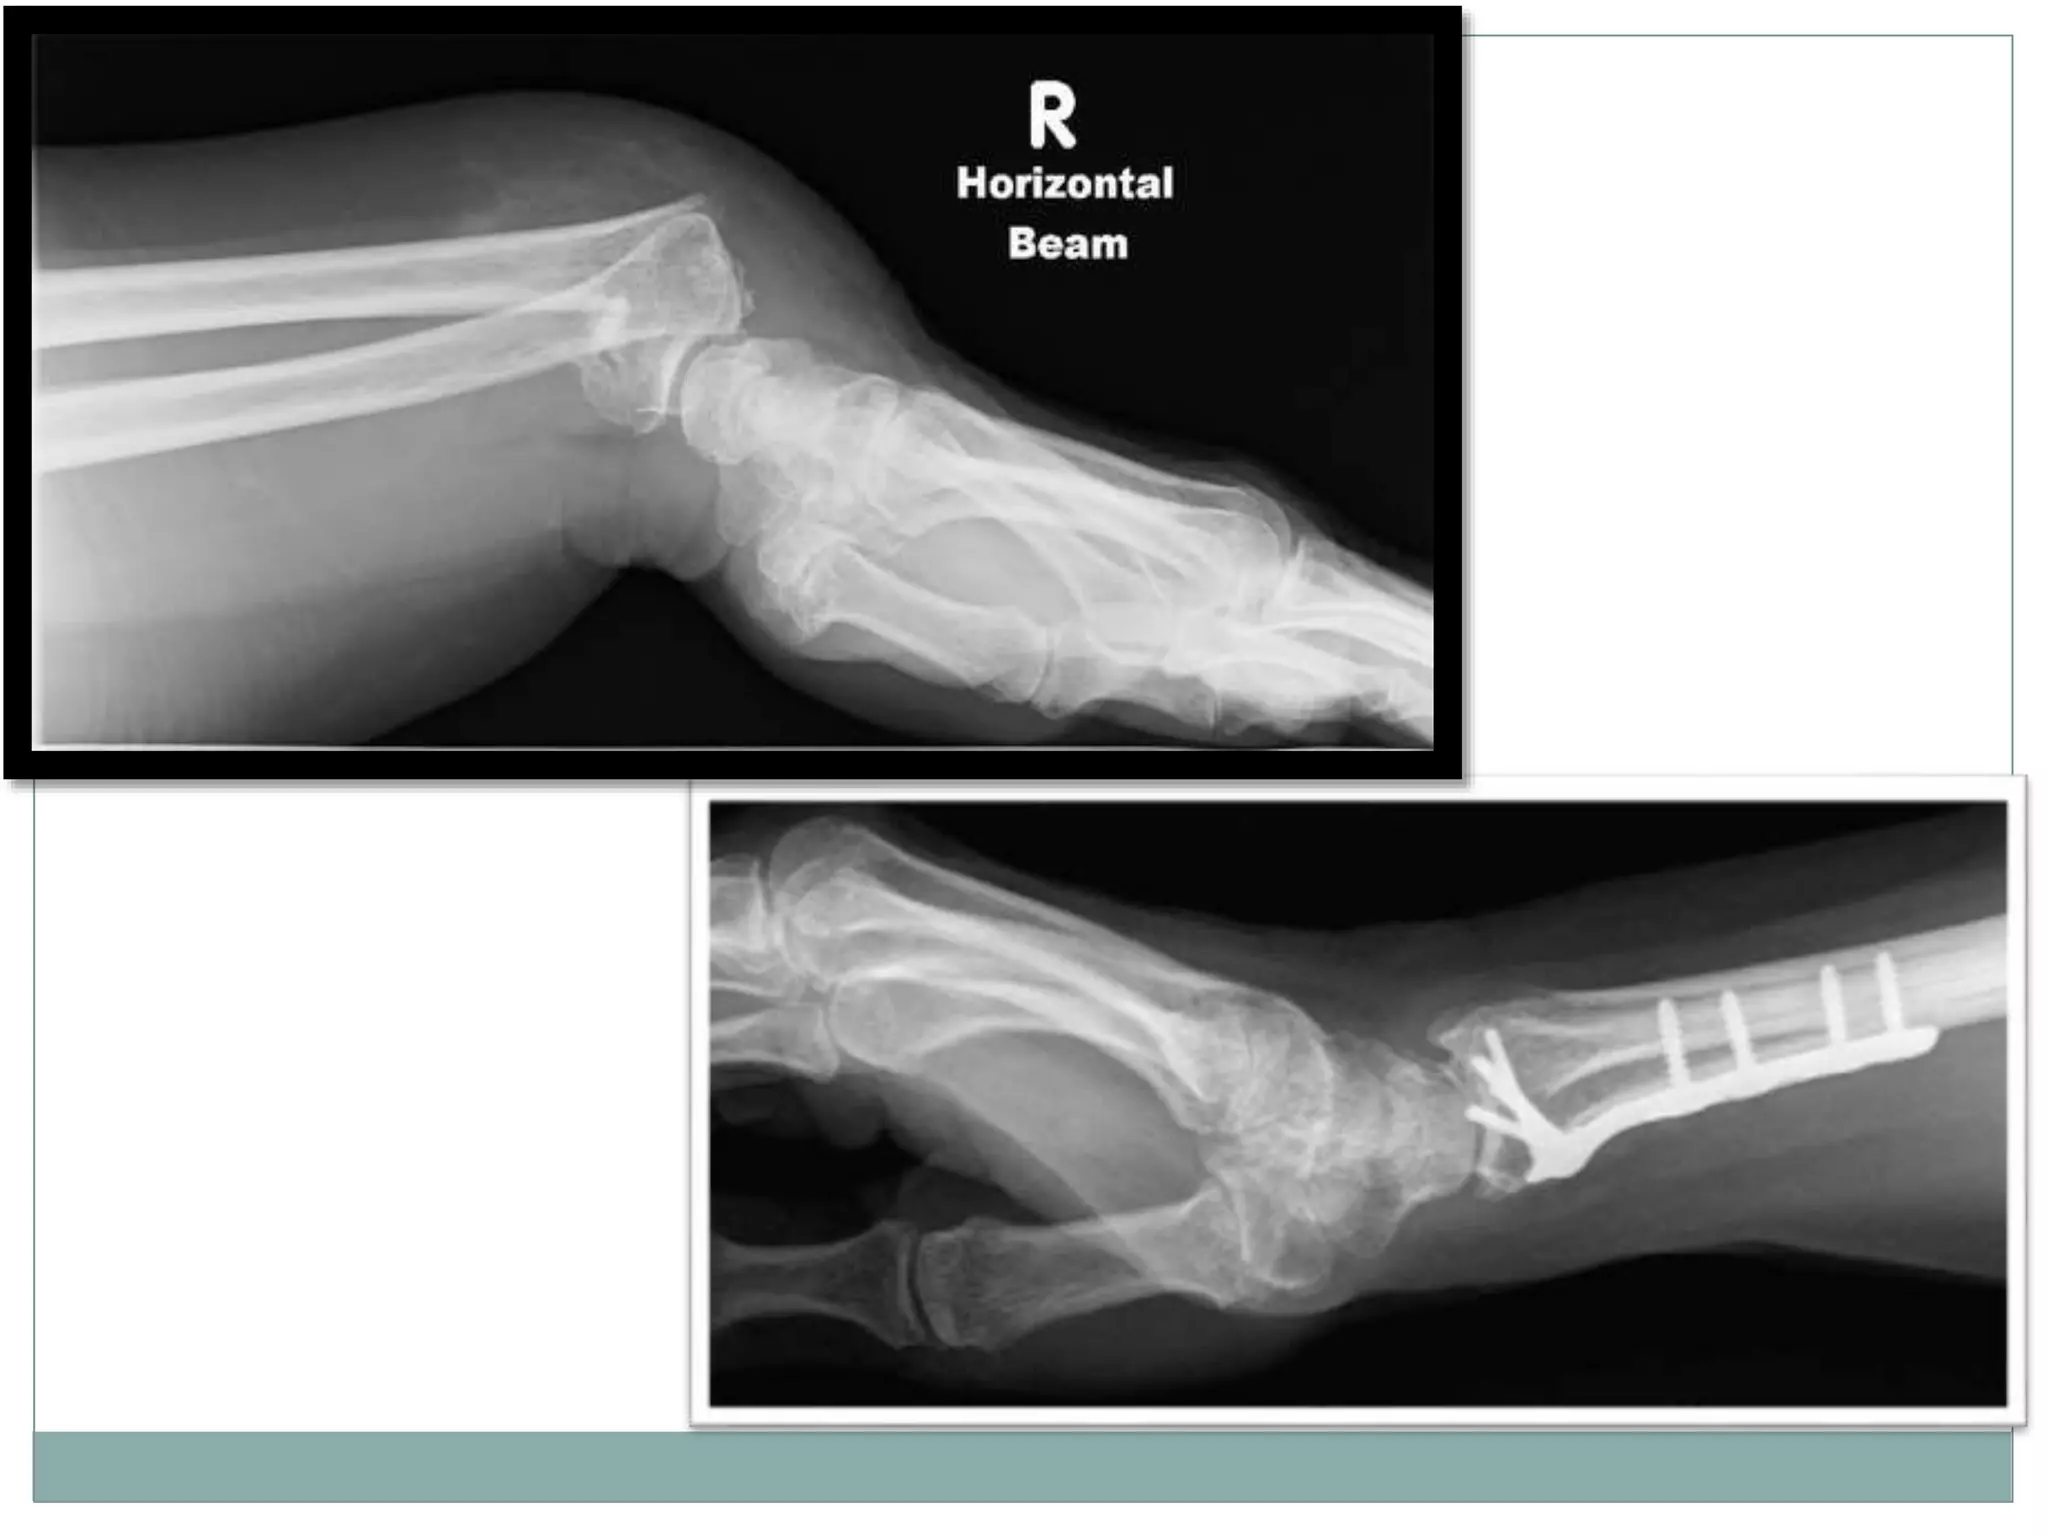

patient is supine

affected arm is placed by the

patient's side on a pillow or

foam block

image receptor is placed

leaning against the

aforementioned foam block

or pillow with the long axis of

the image receptor in line

with the long axis of the

affected limb

Patient Position

Lateral Projection

Centring point

 The ulnar aspect of the mid

carpal region

Collimation

 Antero-posterior to the

skin margins

 distal to the mid way up the

metacarpals

 proximal to include one

quarter of the distal radius

and ulna

Orientation

 landscape

Detector size

 24 cm x 30 cm

Exposure

 50-60 kVp

 3-5 mAs

 There is superimposition of the carpal bones, including the

distal portion of the scaphoid and the pisiform. The radius

and ulna are also superimposed.

patient is supine affectedarm is placed by the patient's side on a pillow or foam block image receptor is placed leaning against the aforementioned foam block or pillow with the long axis of the image receptor in line with the long axis of the affected limb Patient Position

Lateral Projection Centring point The ulnar aspect of the mid carpal region Collimation  Antero-posterior to the skin margins  distal to the mid way up the metacarpals  proximal to include one quarter of the distal radius and ulna

Orientation  landscape Detector size 24 cm x 30 cm Exposure  50-60 kVp  3-5 mAs

 There issuperimposition of the carpal bones, including the distal portion of the scaphoid and the pisiform. The radius and ulna are also superimposed.

• #36 The horizontal beam lateral wrist view is a modified lateral projection when performing the three view series of the wrist and carpal bones in trauma. It is the orthogonal projection of the PA wrist without any patient movement, making it the most appropriate projection for patients in pain.